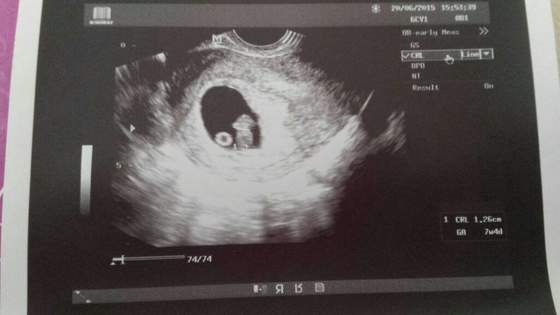

dziewczynki nie słyszałam serduszka ale widziałam zbliżenie jak bije. niestety ten sprzęt nie ma takiej opcji ale lekarka powiedziała ze wszystko ok

ze ciaza się rozwija bardzo dobrze i wogule cała podekscytowana jestem